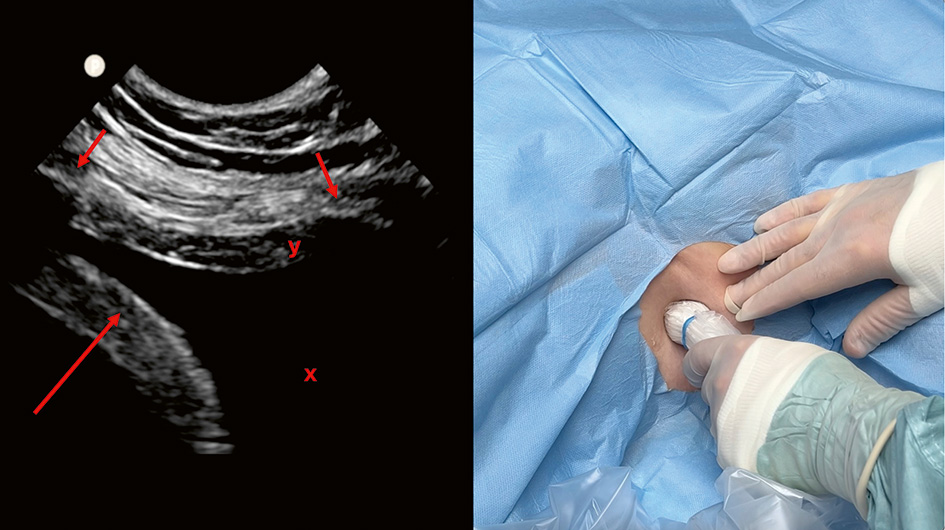

A. Insticksstället identifieras med hjärtprob. I bilden syns mjälten och diafragma (pil) till vänster om pleuravätskan (x). Insticksstället bör vara midaxillärt eller ventralt därom för att undvika trycksår när patienten ligger på rygg.

B. Operatören använder nu en mikrokonvex prob vid insticksstället. I bilden ses två revben (små pilar), diafragma (lång pil) och pleuravätska (x). Interkostala artärer kan ofta visualiseras kaudalt om respektive revben (y).